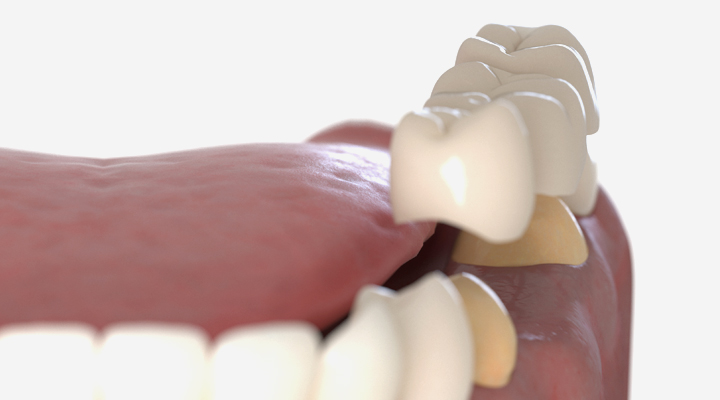

치아가 빠진 경우 양 옆의 치아를 삭제해서 한 세트로 연결해 씌우는 치료입니다.

앞니와 뒷니를 다리(Bridge)처럼 연결하여 빠진 부분의 치아를

새로 달아주어야 하기 때문에 3개의 치아에 연결된 크라운 보철물을 제작해 연결합니다.